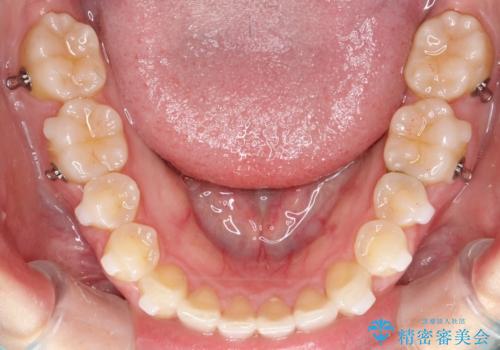

- 前歯のガタガタを綺麗にしたいとのことでインビザラインにて治療を行いました。

治療前は臼歯部反対咬合のため下顎が偏移し正中がずれていましたが、臼歯部反対咬合を改善したことで、正中のズレを改善することができました。